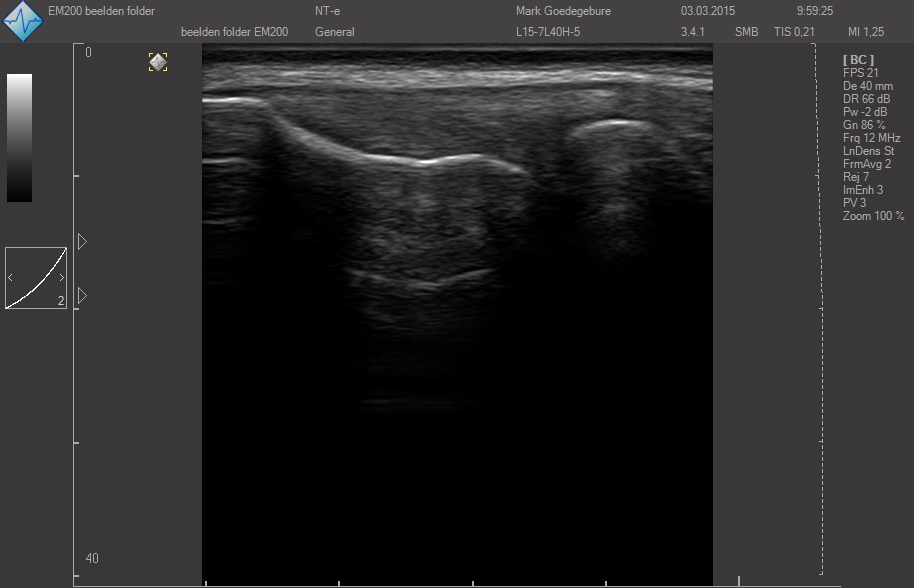

ЗДЕСЬ Вы можете посмотреть реальные кинопетли с аппарата УЗИ SmartUs.